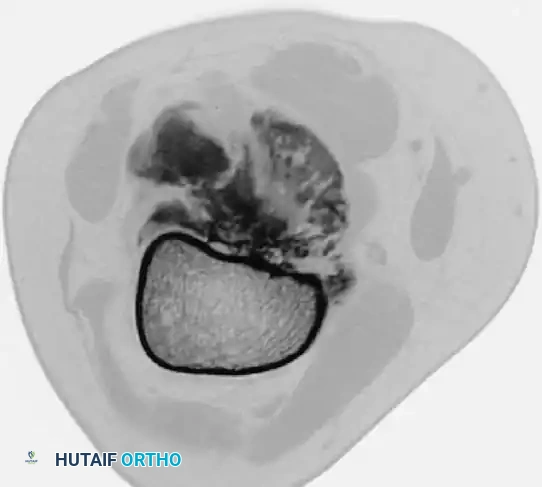

Image

Photograph of the resected distal femur specimen alongside the modular endoprosthetic implant prepared for reconstruction.